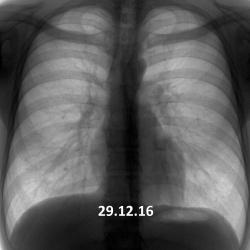

Ж.47 лет, кашель с 3.12.24, темпер-ра до 40 с 23.12.24. Третий курс а/б, без эффекта. Кроме гидроторакса есть значимые изменения в легких?